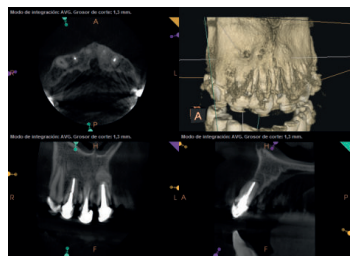

Para confirmar el origen endodóntico y el tamaño de las lesiones se realizaron exploraciones tomográficas con espesor de corte de 75 micras mediante CBCT CS8100 (Carestream Dental® ) en las que se evidenciaron lesiones periapicales radiolúcidas a nivel de 12, 11, 21 (con afectación bicortical), 25 y raíces vestibulares de 26 (Figuras 4 a 8).